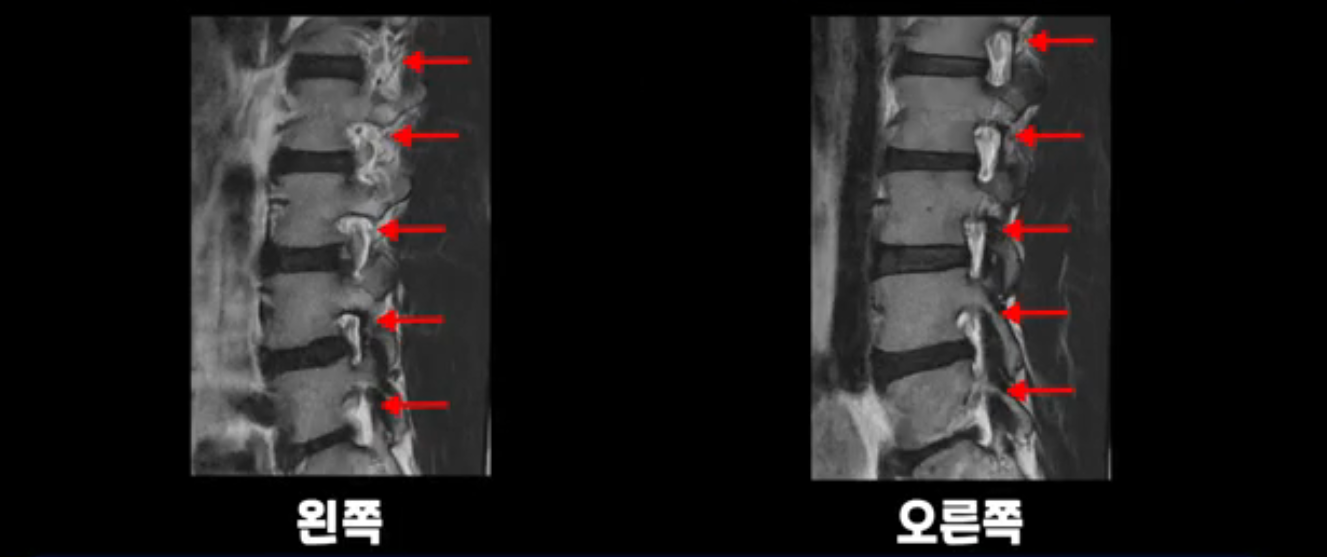

추간공도 보시다시피 왼쪽, 오른쪽 전부 다 매우 넓어서 신경이 눌릴만한 부분이 전혀 보이지 않습니다.